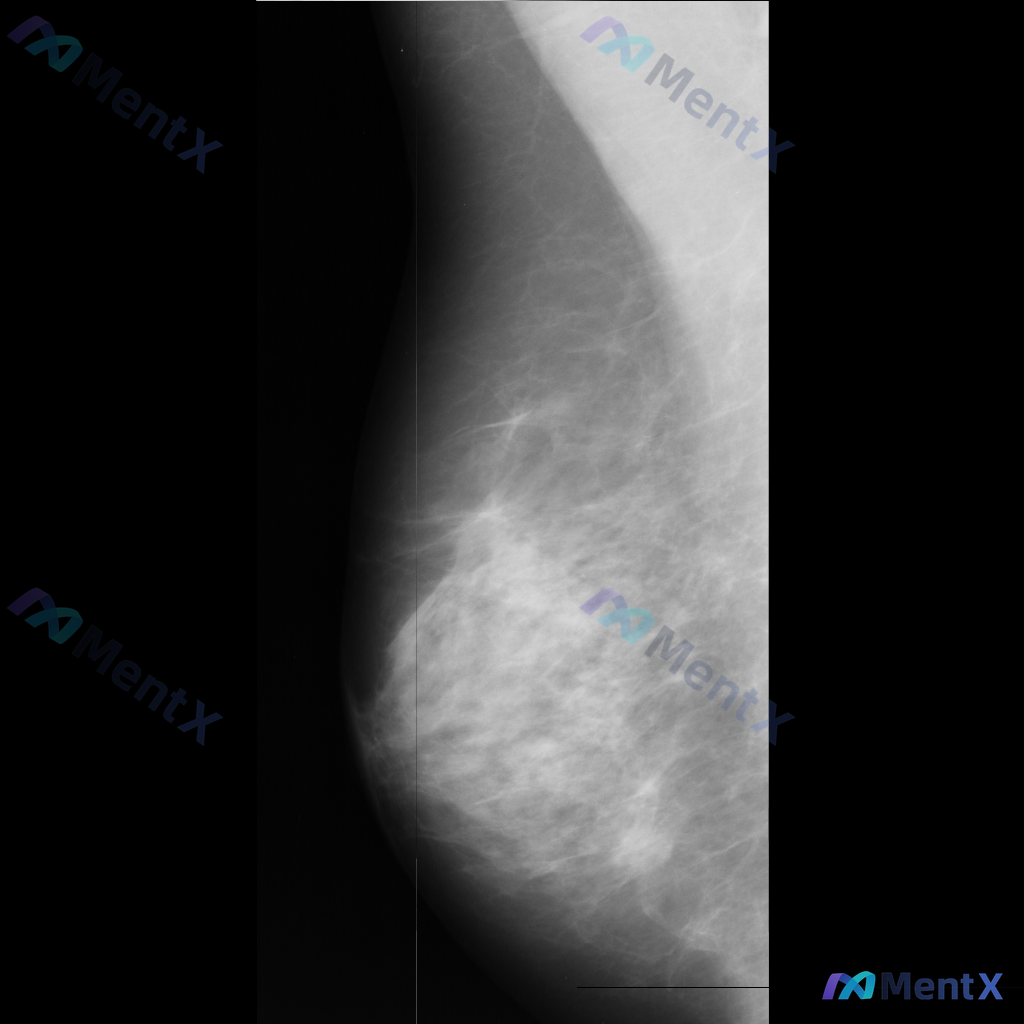

整理了一张乳腺钼靶影像的讨论资料,先和大家分享一下读片描述: 影像可见:不规则、高密度肿块/不对称致密影,伴有毛刺状边缘、结构扭曲和散在钙化。 目前考虑可能存在几种不同的异常方向,想先听听大家的第一反应——单看这组影像特征,你会先往哪种情况考虑? 也可以说说你最关注的是哪一点表现。